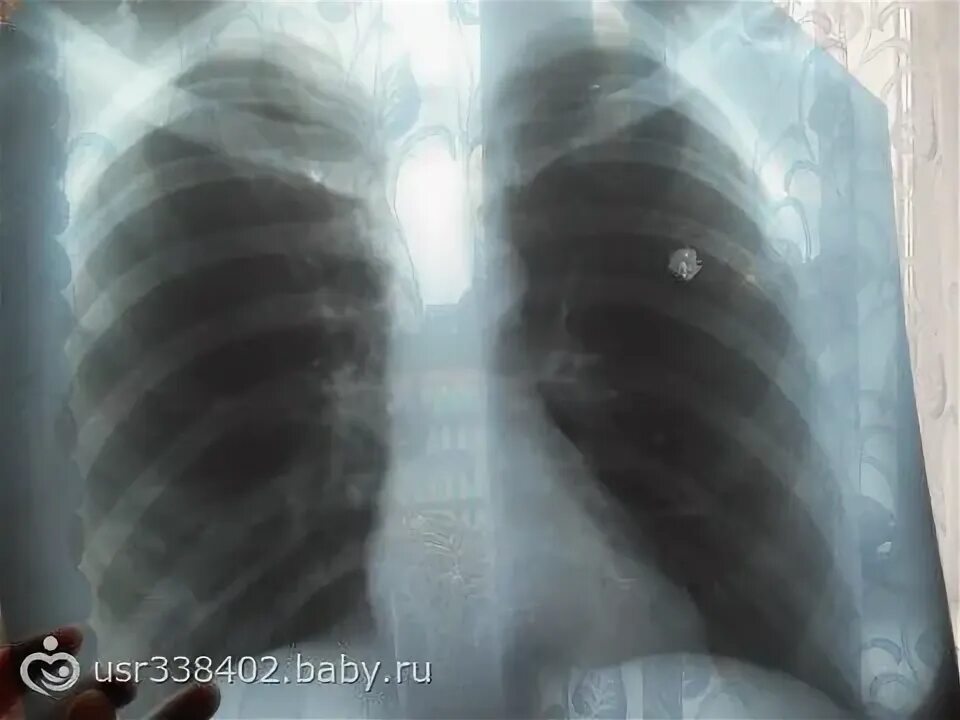

Пятно в легком что это может быть